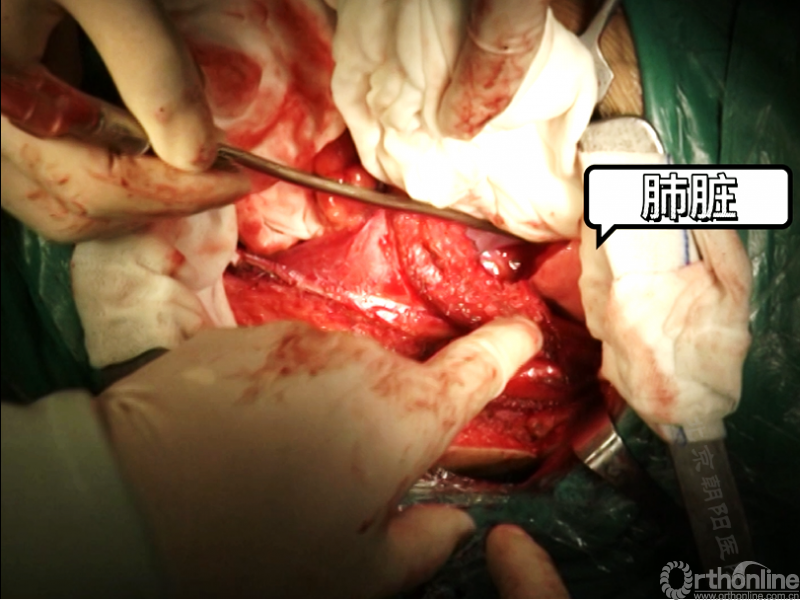

切开横膈进入胸腔侧,术中由双肺呼吸改为凹侧单肺呼吸。

沿脊柱表面纵行切开腹膜,显露腹腔侧,注意避免伤及节段性血管。

在术中神经检测下逐个结扎切断节段动脉,术中注意监测脊髓供血情况。